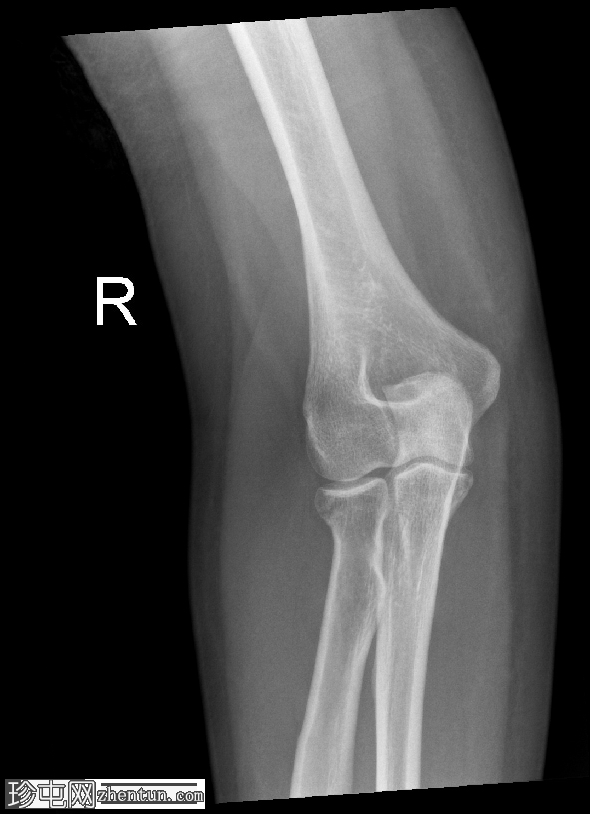

正位

侧位

侧位片显示前后脂肪垫征,提示关节囊扩张。

可见桡骨头轻微凹陷性骨折。

桡骨头骨折通常由肘关节伸直时手掌撑地摔倒所致。侧位X线片上前后脂肪垫征的存在是关节囊扩张(由关节积血和关节积液引起)的重要间接指标,即使皮质骨未见明显损伤,也是隐匿性骨折的标志